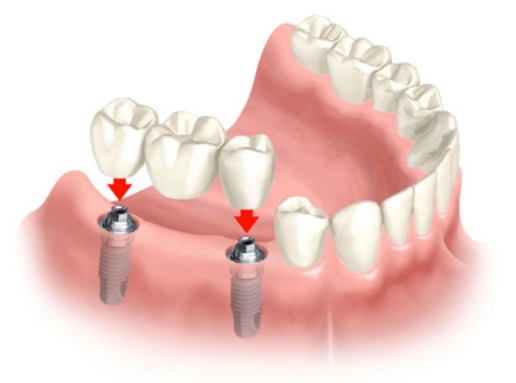

In the long term, implants are aesthetic, functional and comfortable. Gums and bone can recede around a fixed bridge or removable partial denture, leaving a visible defect. Resorbed bone beneath bridges or removable partial dentures can lead to a collapsed, unattractive smile. The cement holding bridges in place can wash out, allowing bacteria to decay teeth that anchor the bridge. In addition, removable partial dentures can move around in the mouth and reduce your ability to eat certain foods.